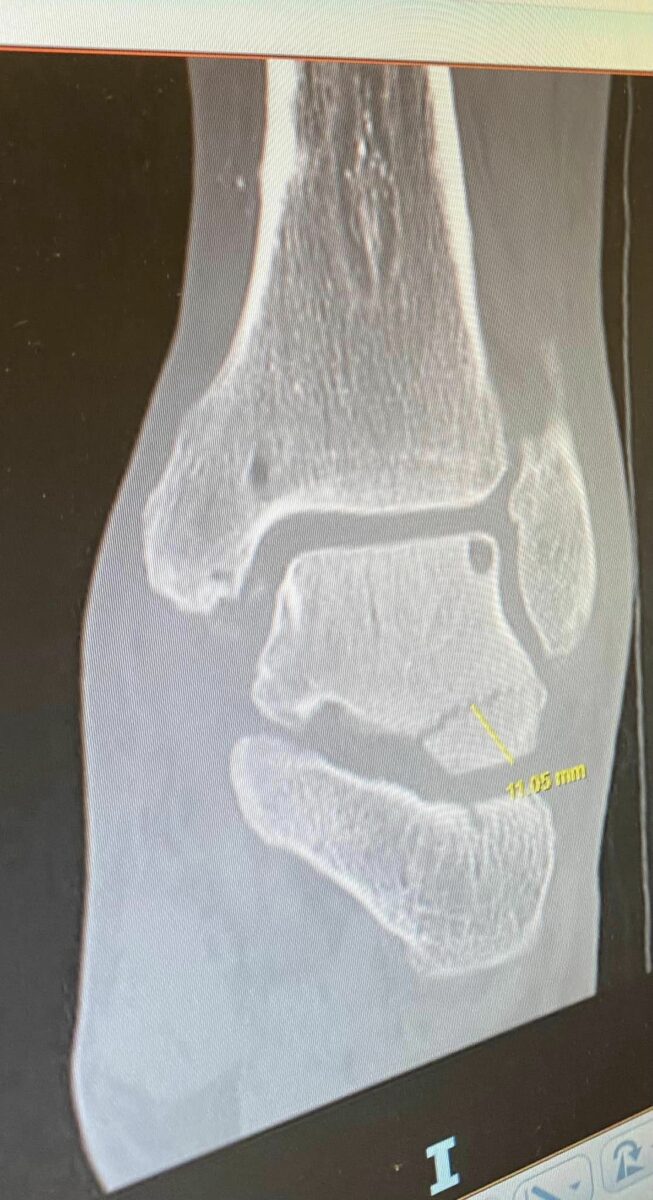

At the first 2023 sidecar GP in Spain, Stuart with new passenger Nathan Cooper, landed short on one of the big jumps, he immediately felt a lot of pain in the ankle, but the local hospital said it was just bruised. He pushed through to the next GP in Portugal, but was still in pain. The pain wasn’t going, and the racing wasn’t any easier, so he sought a second opinion back in the UK only to confirm there was a fracture which now needed an operation. This meant the team had to miss the GPs and even the first round of the British championship.